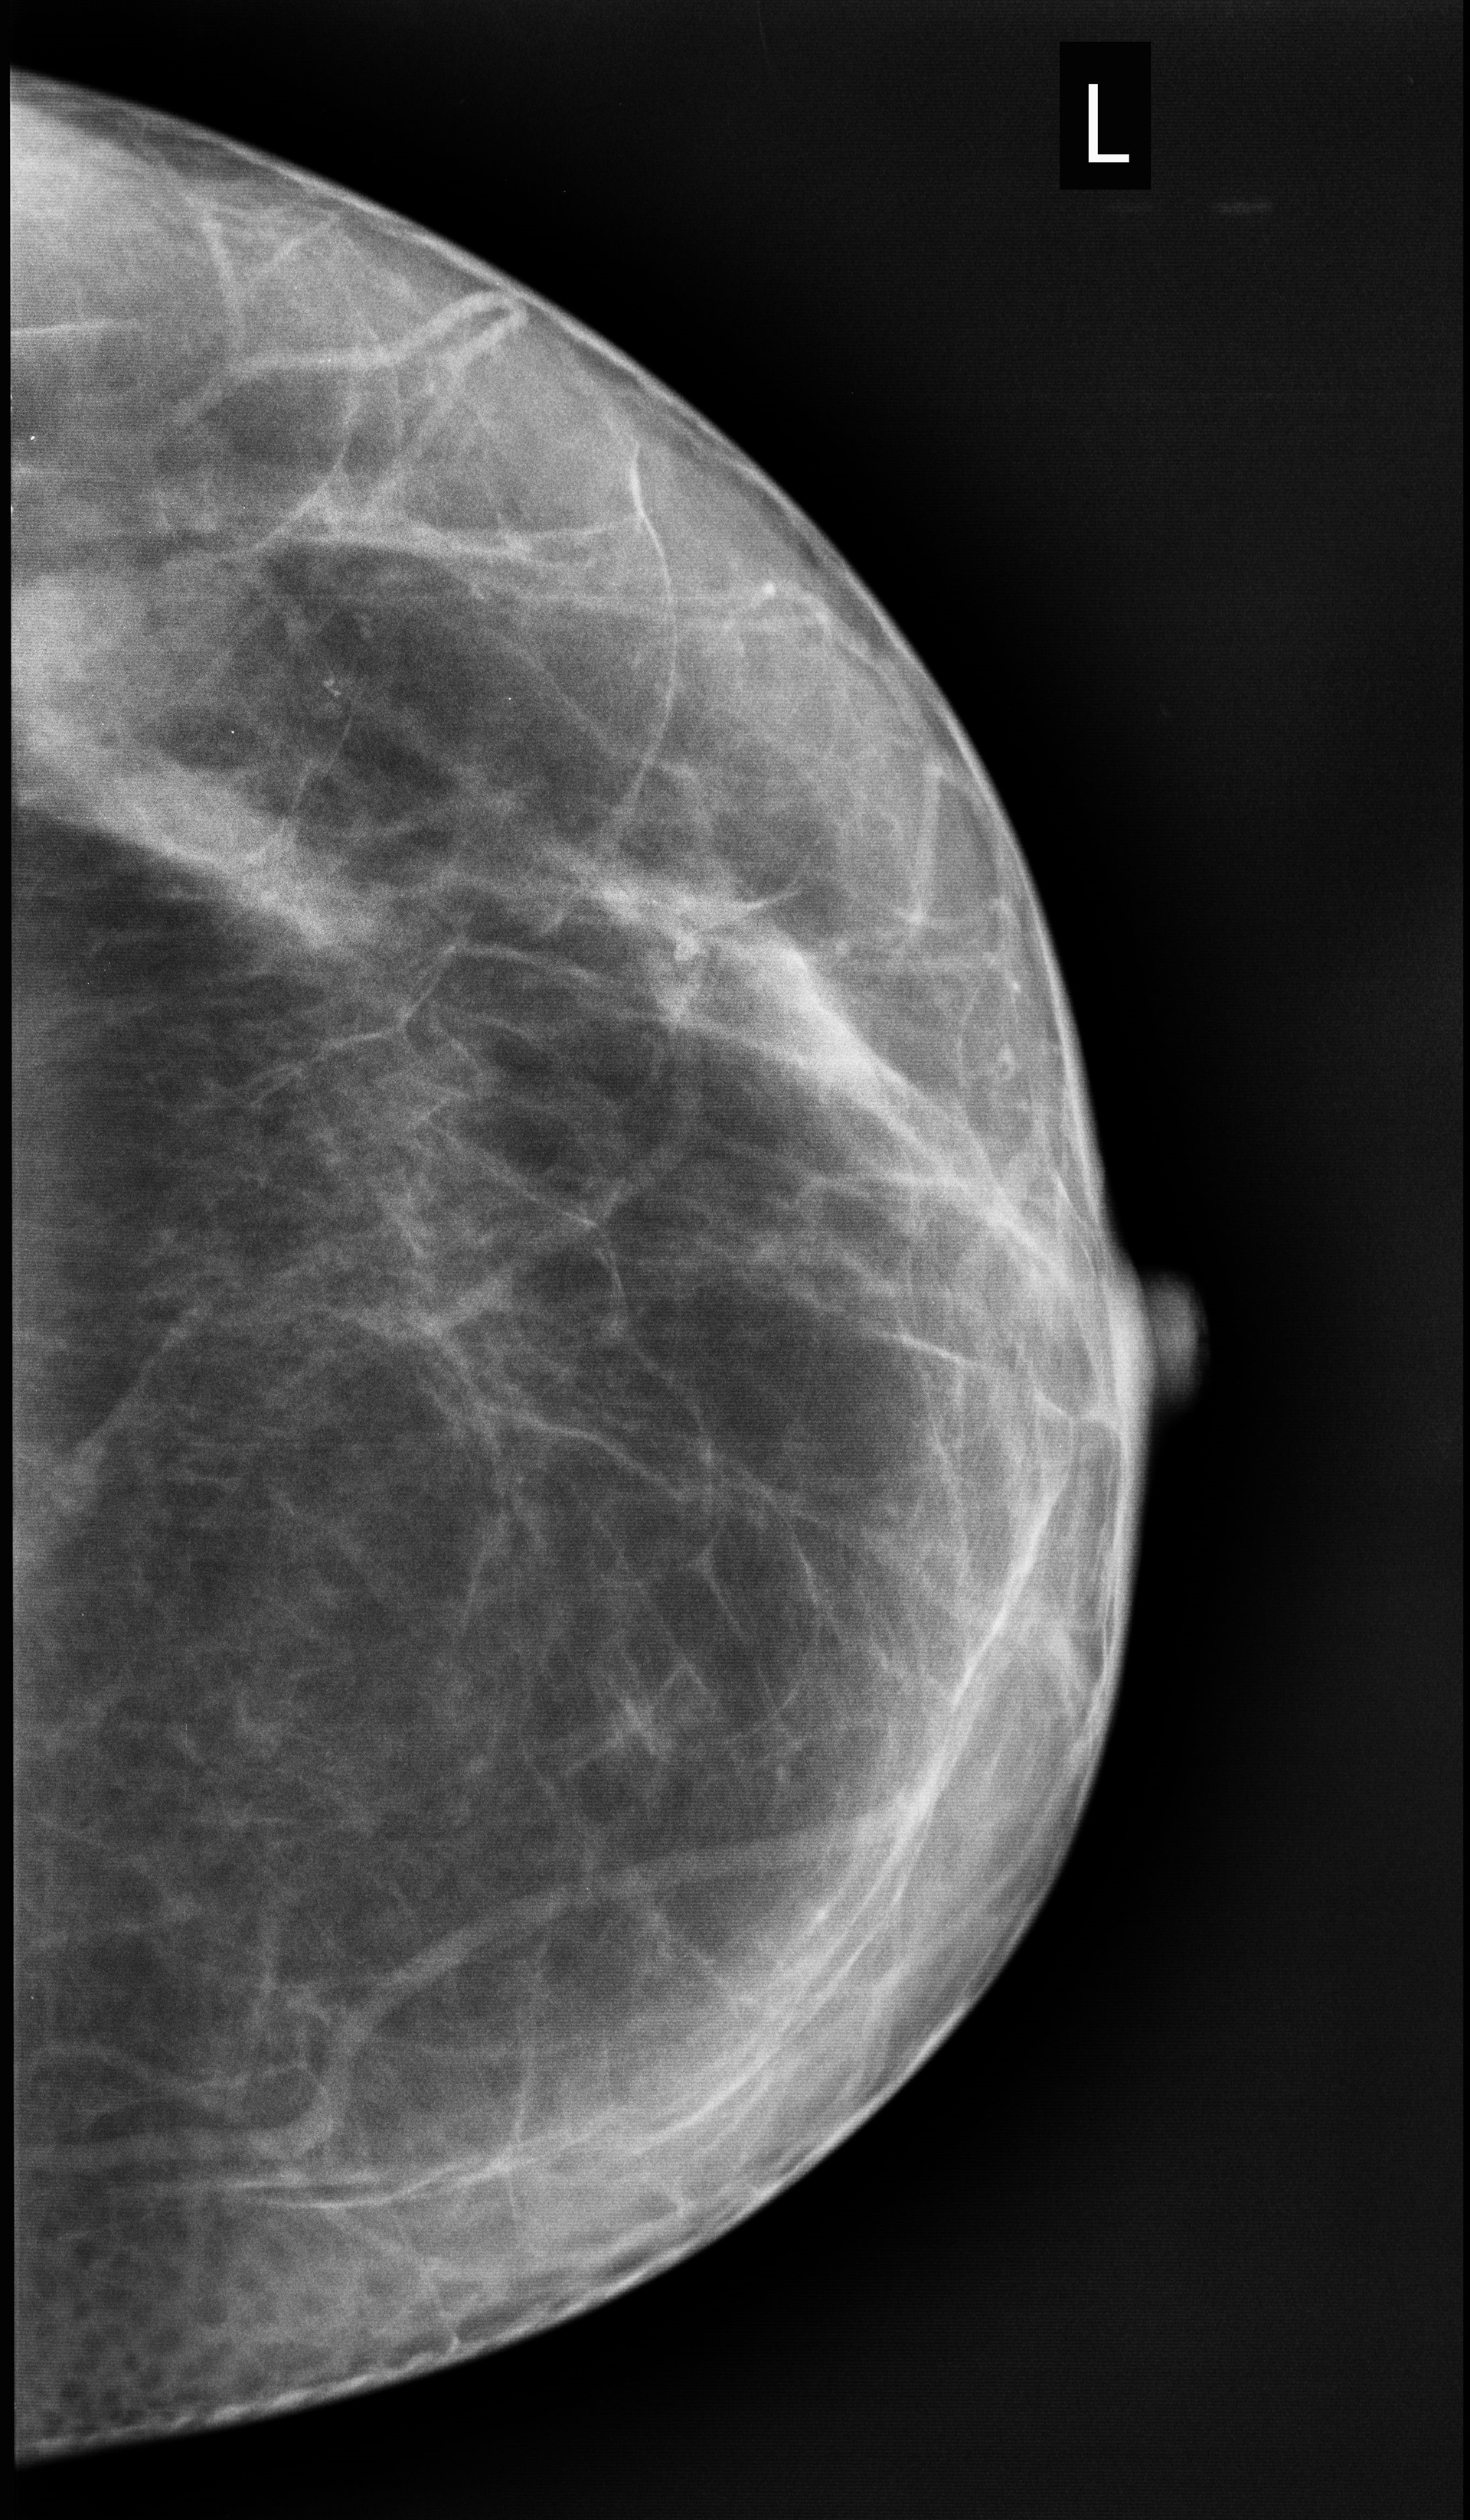

Mamografía

• Mamografía Unilateral

• Mamografía Bilateral